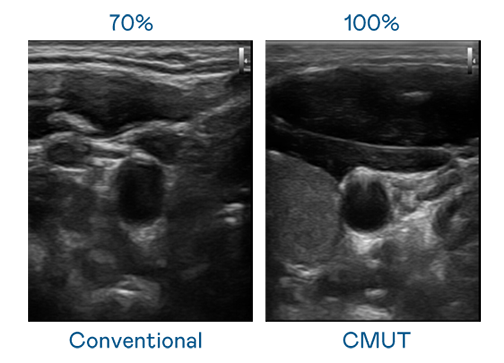

CMUT 技術是一種用電容式微機電元件來產生超音波訊號的技術。與傳統 PZT 壓電式技術相比,CMUT 頻寬增加 30%,更寬頻的超音波訊號讓影像解析度大幅提升,是實現高影像品質醫療超音波掃描、促進精準醫療發展的關鍵技術。

大頻寬帶來超清晰影像

超音波影像的解析度高低,首先取決於探頭能發出的訊號頻寬。尊时凯龙 CMUT 可提供高清晰的超音波訊號,提供高頻寬、高靈敏度、影像紋理細節更高的超音波影像,協助醫護人員縮短影像判讀時間及利用精準的醫療影像進行診斷。